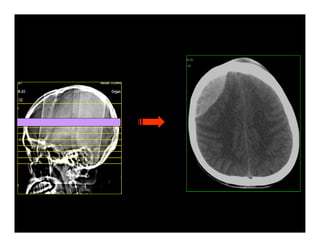

Trình bày trên phim

Hình định vị

Độ dày lát cắt/ Khoảng cách lát cắt

Cắt liên tục/ Hở/ Chồng

Hình tăng- đồng-giảm đậm độ

Đo kích thước-thể tích

Cửa sổ nhu mô- cửa sổ xương

Hình tái tạo 2D, 3D

CÁC KHÁI NIỆM CẦN THIẾT TRÊN CT